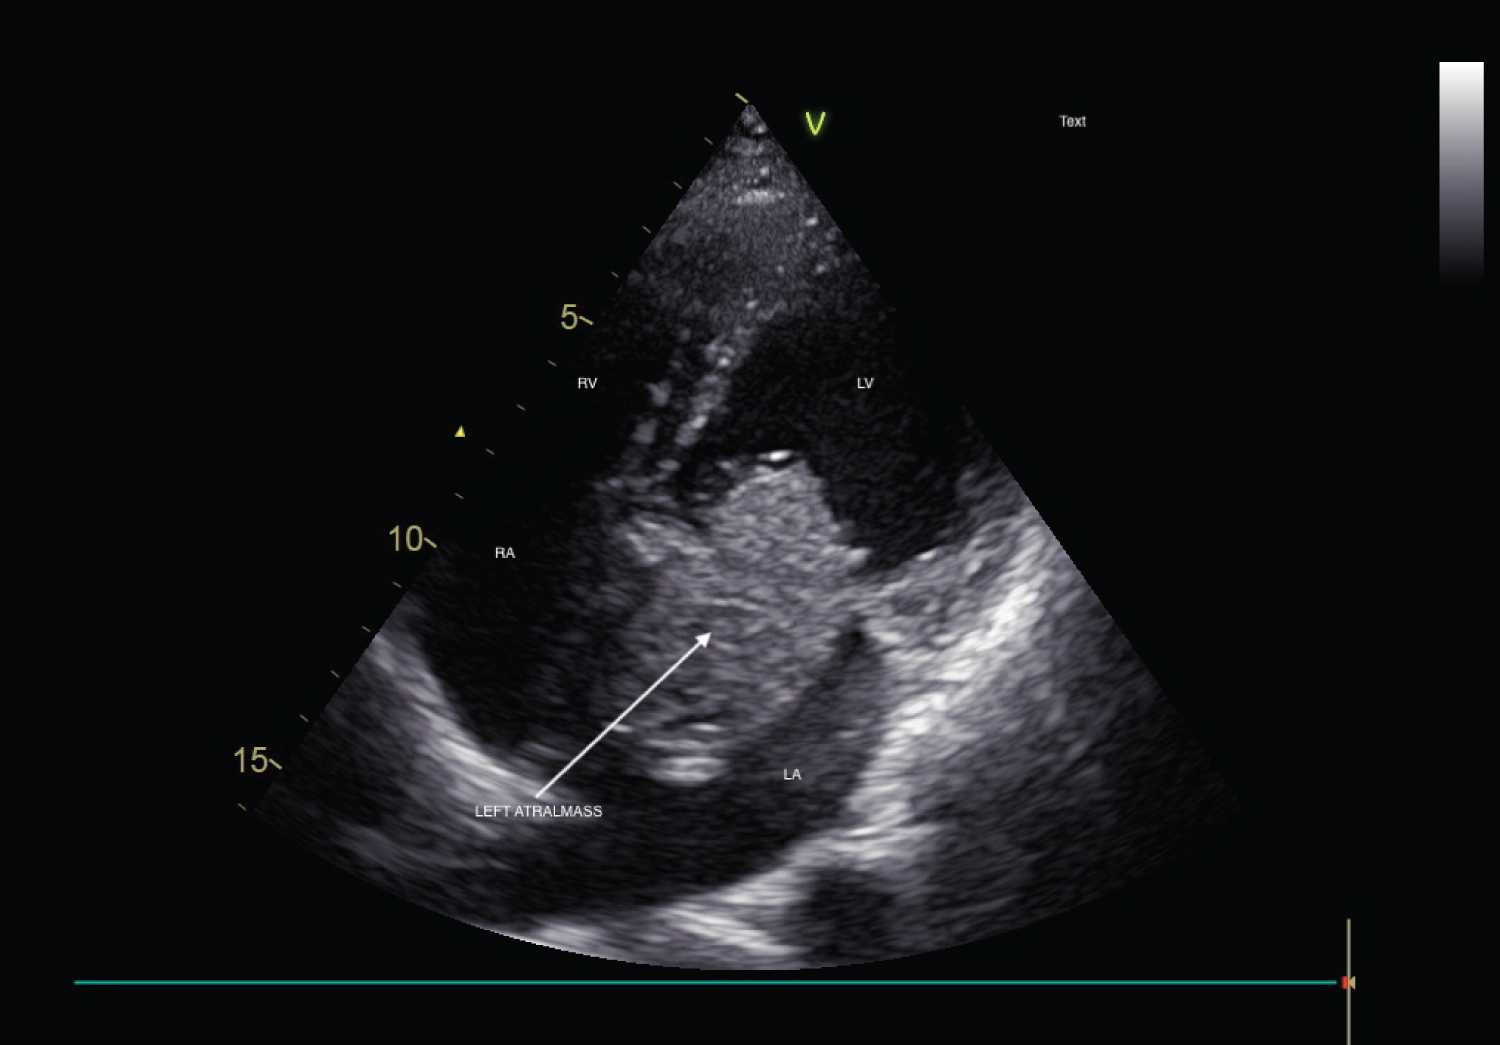

A 45-year-old male was referred to the out-patient clinic of Cardiology department with complaints of recurrent lightheadedness and dizziness on standing and changing postures in bed for past 3 months. He was normotensive, and non-diabetic person with no history of chest pain, dyspnea, palpitations, TIA or stroke. His ECG was unremarkable. CVS examination revealed a low pitch, early diastolic sound along with a soft systolic murmur at the apex. 2D-Echocardiographic study revealed a large, pedunculated mass in the left atrium with stalk attached to fossa ovalis region (Figure 1, Figure 3, Video 1 and Video 2). M-mode echocardiography showed a mass 'plopping' out through LA producing a characteristic multiple diastolic echoes within the mitral orifice as well as systolic echoes within the left atrium (Figure 2). Patient underwent emergency operation for resection of LA mass (Figure 4). Histopathological findings were consistent with myxoma. There was no recurrence of myxoma 6 months post-excision.

Figure 3: Apical 4 chamber view showing large left atrium mass with peduncle attached to fossa ovalis region.